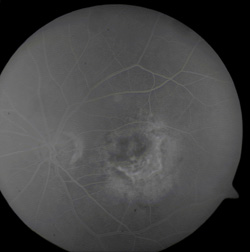

Rycina 1. Postać wysiękowa AMD

Od połowy lat 90. w piśmiennictwie coraz częściej pojawiają się doniesienia o skuteczności metody w niszczeniu patologicznych naczyń podsiatkówkowych (CNV) w zwyrodnieniu starczym plamki żółtej (AMD) czy krótkowzroczności (2,9,15). Klinika Chorób Oczu AM w Warszawie, jako jedna z niewielu w Polsce, zajmuje się tym zagadnieniem. Do leczenia kwalifikujemy głównie pacjentów, u których poddołkowa postać klasyczna AMD zajmuje powyżej 50% całkowitego obszaru zmian oraz z obecnością CNV w wysokiej krótkowzroczności. Przed terapią oraz na wizytach kontrolnych pacjenci mają wykonywane badania: pełne badanie okulistyczne z barwnym zdjęciem dna oka, OCT, komputerowy test czułości siatkówki na kontrast (Lagon SCM Test), angiografię fluoresceinową uzupełnianą czasami angiografią indocjaninową.

Rola PDT polega na niszczeniu patologicznych naczyń podsiatkówkowych (CNV) przy użyciu podanego dożylnie związku fotouczulającego i promieniowania laserowego o niskiej mocy, które aktywuje związek skumulowany w patologicznych naczyniach. Przez wiele lat w takich przypadkach stosowano fotokoagulację laserową, ale tylko około 13- 26% pacjentów z CNV reagowało na leczenie, z czego około 50% leczonych miało nawrót przecieku. Z teoretycznego punktu widzenia jest duża przewaga PDT nad laserem konwencjonalnym. Ten ostatni działa termicznie, powodując obliterację nowotwórstwa podsiatkówkowego i zniszczenie leżącej powyżej sensorycznej siatkówki, podczas gdy metoda fotodynamiczna jest bardziej selektywna - dokładnie lokalizuje barwnik w obrębie CNV. Ponadto dawki promieniowania potrzebnego w leczeniu są dużo niższe niż wymagane do fotokoagulacji laserowej.

Nasze dotychczasowe wyniki oraz dane z literatury wskazują, że PDT bardziej zmniejsza ryzyko utraty widzenia niż stwarza możliwość polepszenia ostrości wzroku. Równocześnie zaznaczyć należy, że jest to leczenie wieloetapowe, częstość którego wyznacza przeciek z naczyń widoczny w angiografi fluoresceinowej.